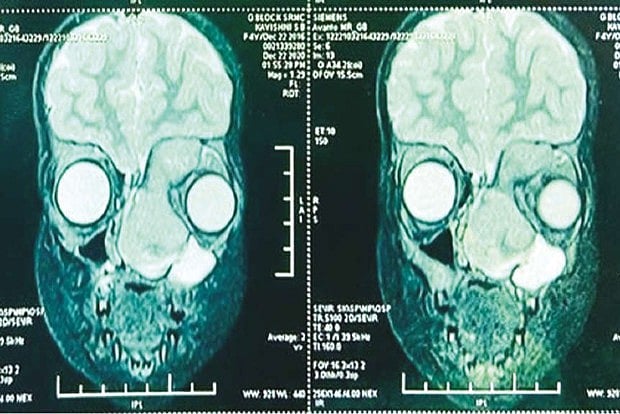

The scan shows the tumour in a 4-year-old girl?s nasal passage progressing towards her left eye

Despite treatment, the tumour had grown and blocked both nasal passages. It had also extended into the poor girl’s left eye and was displacing it “outwards and downwards.” Further Investigations by expert doctors at SRM revealed a very extensive tumour in the left nasal cavity with extension into the left eye, engulfing the left eyeball and displacing the eye outwards.